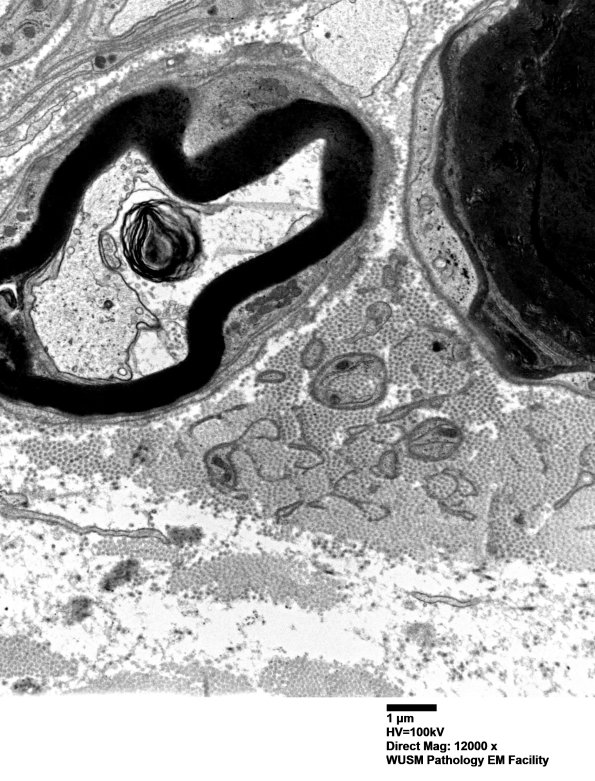

6B2-4 Basal lamina free of axons and collagen pockets mark the prior distribution and loss of unmyelinated axons. (Electron micrographs)